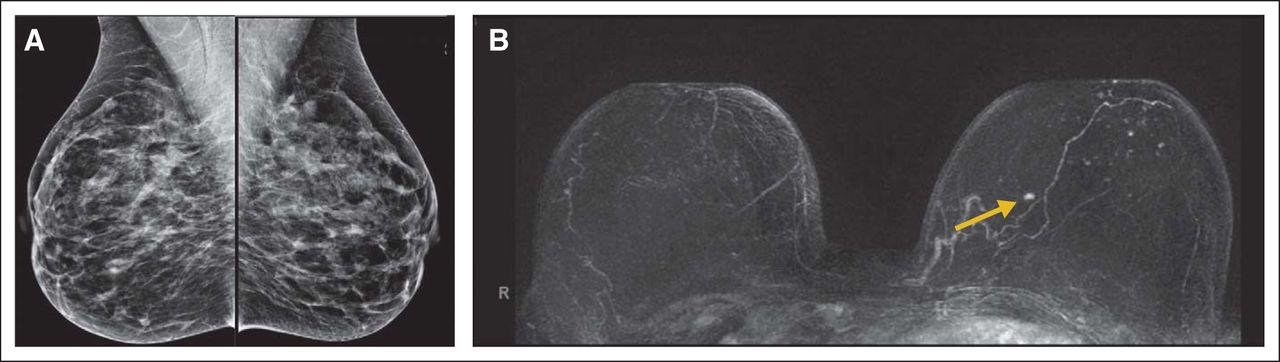

- All were asymptomatic and had negative or benign mammogram at time of MRI

- All had (false) negative or benign mammograms

- 10 of 11 had (false) negative or benign US, 11th had negative targeted US at site of MRI detected cancer